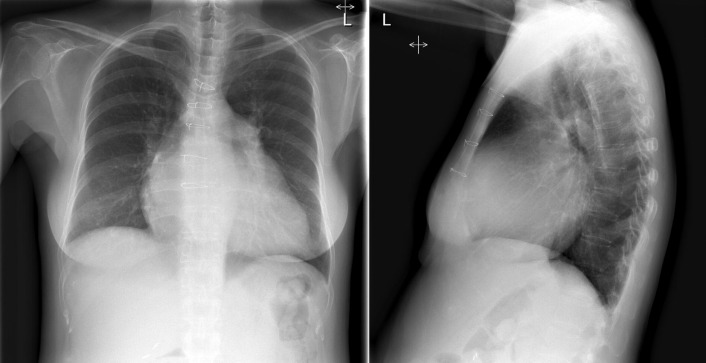

Enlargement of the left atrium is present in the majority of cases of hypertrophic cardiomyopathy ( Figs 14-1 to 14-4 ). Left atrial enlargement is greater in patients with hypertrophic cardiomyopathy when there is concurrent mitral insufficiency. The degree of left ventricular enlargement is variable but is usually mild and consistent with left ventricular hypertrophy. About 50% of cases have cardiomegaly, usually mild to moderate. Mitral annular calcification is common.